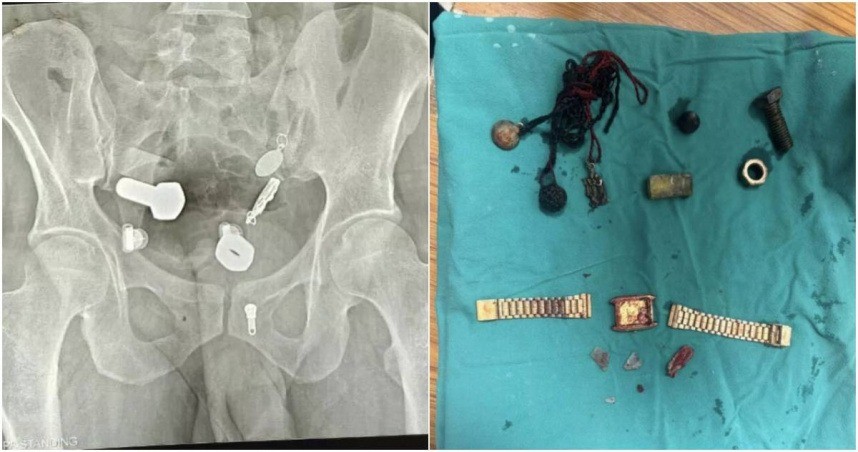

Theo Mirror, một người đàn ông ở Ấn Độ được đưa đến Bệnh viện Sawai Mansingh tại thành phố Jaipur trong tình trạng đau bụng dữ dội, cơ thể suy kiệt vì không thể ăn uống trong nhiều ngày. Ban đầu, các bác sĩ nghi ngờ anh chỉ gặp vấn đề tiêu hóa thông thường, nhưng kết quả chụp X-quang đã khiến tất cả phải kinh ngạc.

Bức ảnh phim cho thấy rõ ràng trong bụng bệnh nhân có những vật thể kim loại — bao gồm một chiếc đồng hồ đeo tay, cùng bu lông và ốc vít gắn chặt với nhau.

Các bác sĩ đã thử dùng ống nội soi để gắp dị vật ra ngoài nhưng không thành công, buộc phải tiến hành phẫu thuật mở ổ bụng. Cuộc phẫu thuật kéo dài hơn ba giờ, các bác sĩ đã lấy ra toàn bộ vật thể nằm trong dạ dày và ruột bệnh nhân.

Theo Khaosod, ê-kíp y tế mô tả khoảnh khắc nhìn thấy chiếc đồng hồ trong bụng bệnh nhân là “cú sốc thực sự”. Sau phẫu thuật, sức khỏe của người đàn ông dần ổn định, hiện đang hồi phục tốt.

Đau bụng suốt nhiều ngày, người đàn ông bàng hoàng khi bác sĩ gắp ra... đồng hồ và nhiều dị vật khác. Ảnh: Mirror